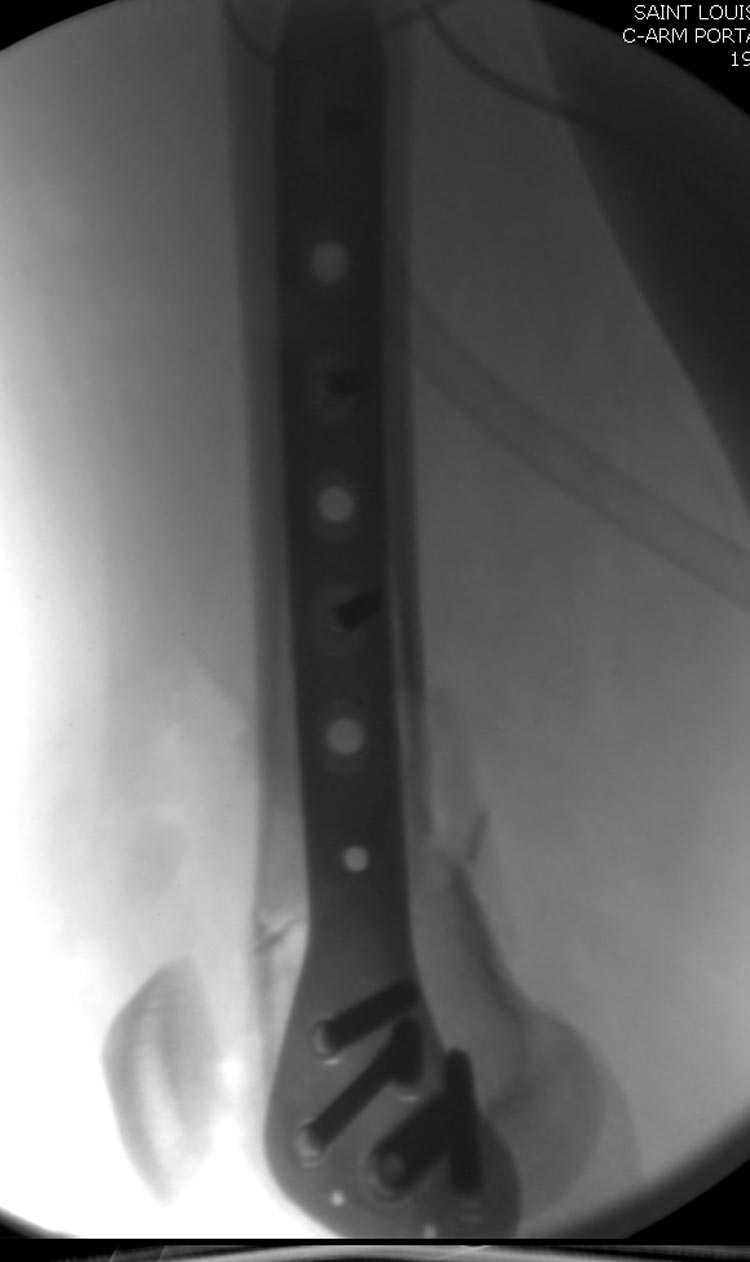

Бесспорно, предлагаемый ретроградный метод имеет свои преимущества, но имеется опасность при манипуляции интрамедуллярным гвоздем расколоть мыщелки.

Раскол можно предупредить шурупами, но короткий дистальный фрагмент навряд ли позволит добиться адекватной стабильности конструкции. Стандартные гвозди не рассчитаны для таких переломов, и если все таки желаете провести фиксацию гвоздем, тогда надо заказывать специальный custom made nail т.е. с расширенной возможностью дистальной блокировки.

Почти все компании имеют пластины с угловой стабильностью, начиная от Stryker, Zimmer NCB и DePuy Polyaxial Plate . Если у NCB шуруп блокируется специальной шайбой, то Polyaxial Plate имеет вариабельный угол введения шурупов.

Поэтому такие меж и над- мыщелковые переломы более предпочтительным считается фиксировать мыщелковыми пластинами

Устанавливается из малого разреза "не вскрывая сустав" со стороны латерального мыщелка, и Insertion Jig позволяет установить пластину "мостовидно" перкутанно в проксимальном отделе, "не вскрывая и не трогая" место перелома.